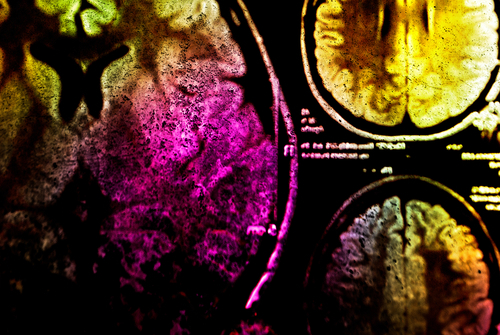

Multicolour MRIs could improve disease diagnosis

Researchers have developed a method that could make magnetic resonance imaging - MRI - multicolour and help improve disease diagnosis.

Current MRI techniques rely on a single contrast agent injected into a patient's veins to vivify images.The new method uses two at once, which could allow doctors to map multiple characteristics of a patient's internal organs in a single MRI. The strategy could serve as a research tool and even aid disease diagnosis."The method we developed enables, for the first time, the simultaneous detection of two different MRI contrast agents," said Chris Flask, Associate Professor at Case Western Reserve University School of Medicine in Cleveland, Ohio, US. Two contrast agents could include one specifically targetting diseased tissue, and one designed to show healthy tissue, for example. The new method would enable immediate comparisons of how each agent distributes in the same patient.

"This multi-agent detection capability has the potential to transform molecular imaging, as it provides a critical translational pathway for studies in patients," said Flask.In a study published in the journal Scientific Reports, the researchers described how two contrast agents, gadolinium and manganese, can be detected and independently quantified during MRIs. The results provide "an adaptable, quantitative imaging framework to assess two MRI contrast agents simultaneously for a wide variety of imaging applications", the researchers said."In this initial paper, we validated our new methodology, opening the possibility for numerous follow-on application studies in cancer, genetic diseases such as cystic fibrosis, and metabolic diseases such as diabetes," Flask said.